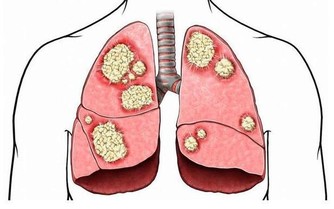

信號五:腳趾甲異常

△健康徵兆:

1、趾甲厚重發黃:可能由於黴菌感染而引起,糖尿病患者、有循環問題和免疫系統問題的人容易感染該疾病;

2、趾甲有凹痕:可能由於微量元素缺乏所引起,也有可能是其他疾病,

如牛皮癬關節炎,表現為指甲有很多小洞,可深可淺。